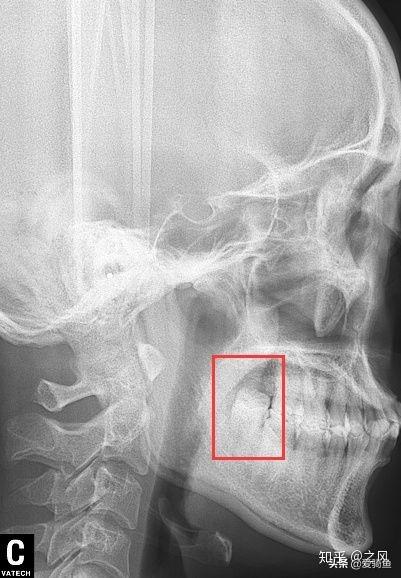

排隊(duì)等待叫號(hào),進(jìn)去后張嘴檢查下,讓去拍片子,應(yīng)該就是我之前去的其他牙診所機(jī)構(gòu)的口掃,這里沒(méi)有給我電子照片,下面是以前拍的。

口掃

智齒

拍好片子后,去就診,房間里一個(gè)主治醫(yī)生,一個(gè)年輕女幫手,主治醫(yī)生看片子廢話不多說(shuō),安排你躺下,燈照著你,告訴你別緊張,說(shuō)“緊張就別拔了”,然后打麻藥,三分鐘左右吧右下半部分臉就麻木了。然后拿一個(gè)錘子一個(gè)鑿子,砰砰砰鑿、撬起來(lái)了,雖然不疼但這陣仗會(huì)讓人緊張起來(lái),然后醫(yī)生就會(huì)說(shuō)你,”別緊張,放松,越緊張?jiān)诫y拔“,估計(jì)不到2分鐘一顆智齒就給拔下來(lái)了,然后半分鐘給你縫了線。 給你塞了一個(gè)止血棉讓你咬住。